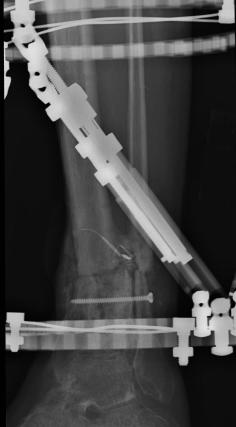

Pre-corrective surgery X-Rays of the damaged right & left legs / ankles

These x-rays were taken at Dr Armendariz’s office, just prior to performing any corrective surgery. As can be seen in these images,

there was no tibia bracing provided by Dr. Keller. Liam was released from Dr Keller’s care with instructions that full weight bearing could

be accomplished within 2 months of Keller’s last surgical procedure. The best example to examine is the second image (from the left) of the

top how. Notice how the bones that should be aligned with the tibia are in fact on the other side of the leg. The third image shows how badly

Liam’s left foot was twisted as a result of the pool placement of the external fixation. What is not obvious is that the screw at the bottom

of the plate on the right fibula missed being screwed into the plate.